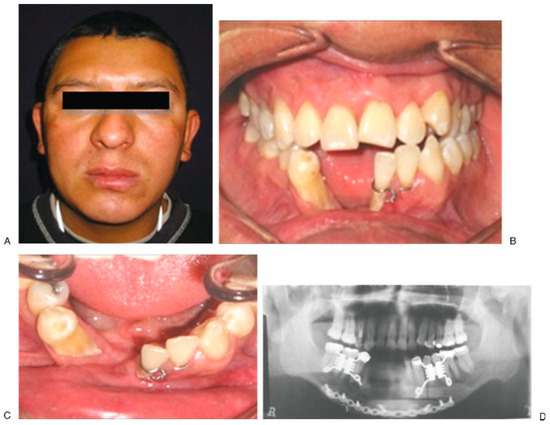

Figure 6. Initial aspect (A–E); closing of alveolar fistula at 37 weeks of follow-up (F–I). - Case 5 was a 13-year-old female patient with dysmorphic syndrome, cleft lip and palate sequel, and active oronasal fistula, treated with trifocal ABT (Figure 7).

Figure 7. Initial aspect (A,B), active oronasal communication. Note the congenital edentulism (C,D). End alveolar bone transportation technique, with bone and dental anchorage used (E); at 228 weeks of follow-up without evidence of communication (F,G). - Case 6 was a 26-year-old male patient with facial gunshot sequel, treated with trifocal ABT (Figure 8).